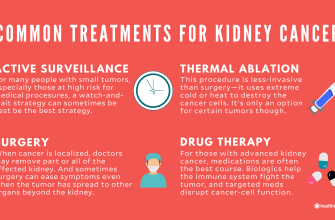

Kidney tumors, also known as renal tumors, are abnormal